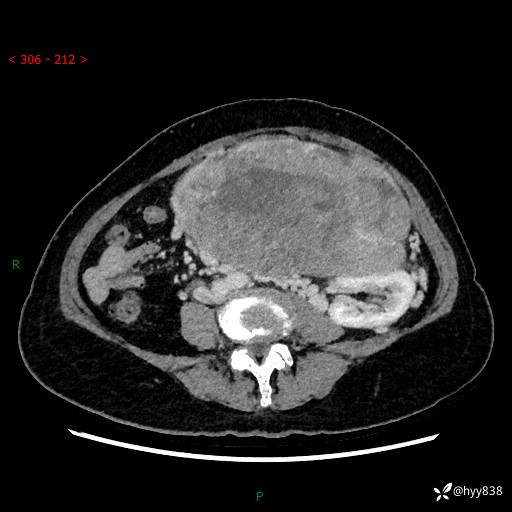

据说只有腹膜后,才能见到如此巨大的肿块---(有结果)

主诉:发现腹膜后占位1周

简要病史:患者1周前因头晕在当地第二人民医院检查发现左侧腹膜后区巨大富血供占位性病变,患者自诉腹部稍硬,无其他不适,无血尿,无腰痛等不适,患者为求进一步治疗来我院,门诊以“腹膜后占位性病变”收入我科。 起病以来,患者精神、饮食、睡眠可,大便正常,小便如上述,体力体重无明显改变。

临床诊断:腹膜后占位

腹部CT增强(动脉期+静脉期 ) ---平扫外院